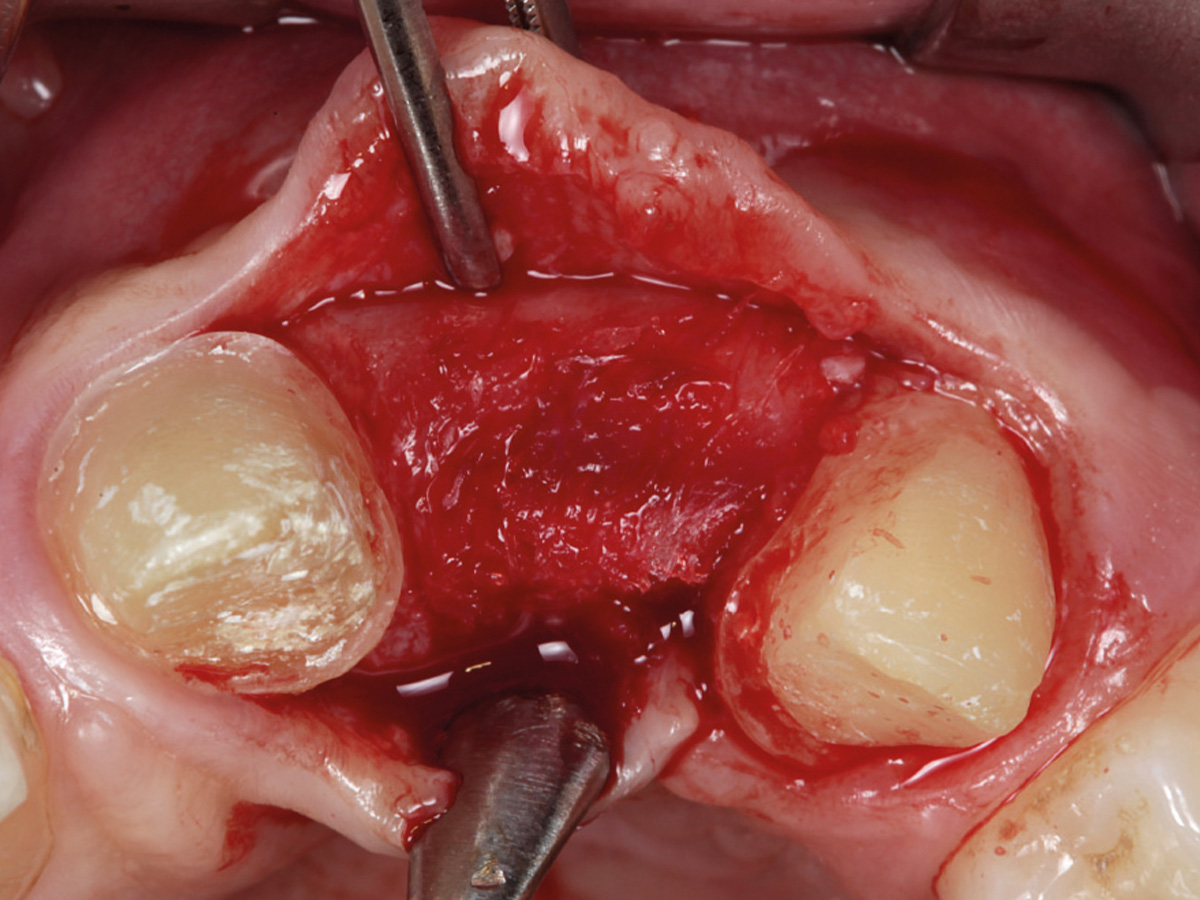

Abbildung 10

Regenerierter Bereich nach Lappenbildung. Gewebe gut durchblutet, Reste der Lamina sichtbar.